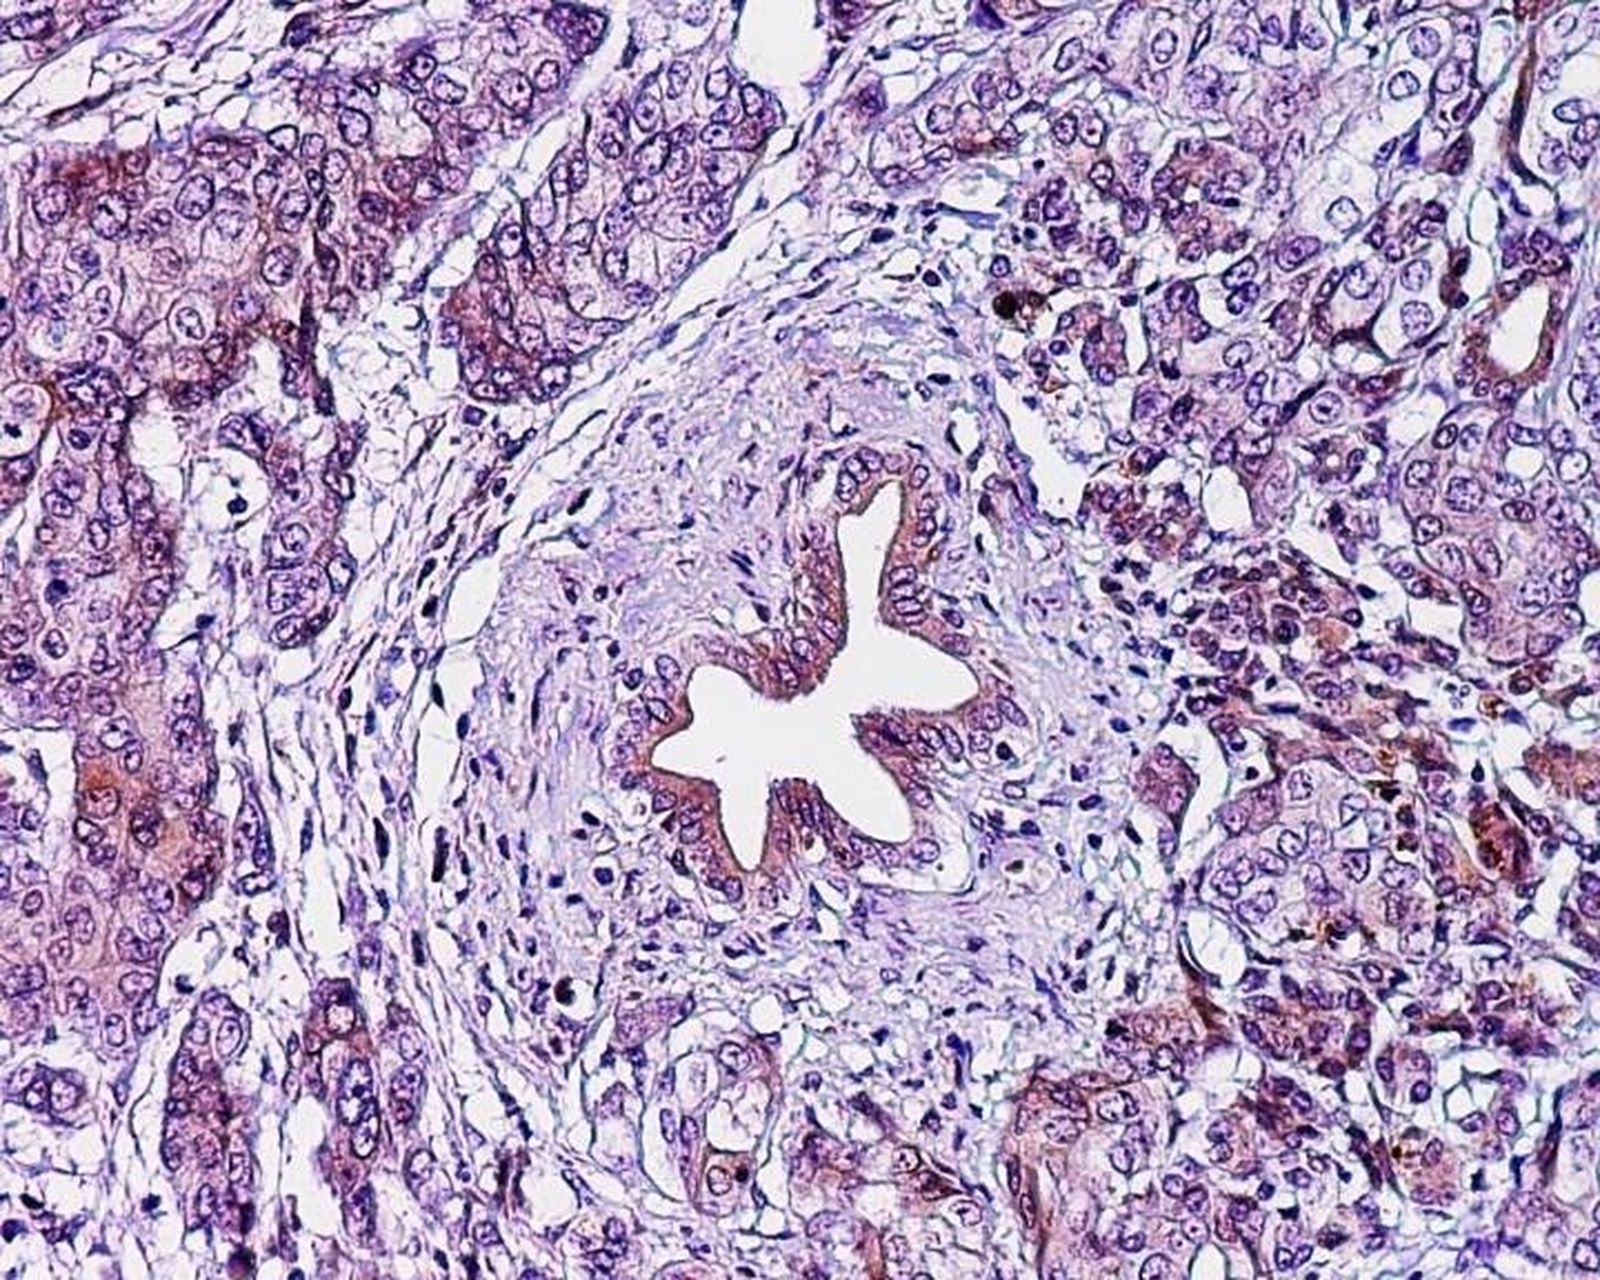

Investigadores de la Universidad de Tel Aviv en Israel están trabajando en una nueva molécula capaz de "erradicar eficientemente" las células de cáncer de páncreas desencadenando su autodestrucción, según han observado en un estudio realizado con xenoinjertos, es decir trasplantes de cáncer de páncreas humano en ratones inmunocomprometidos.

Este nuevo tratamiento redujo el número de células cancerosas en un 90 por ciento en los tumores desarrollados un mes después de la administración. Este resultado ha llevado a los investigadores a calificar de "prometedores" las primeras conclusiones.

Los ratones fueron tratados con una molécula llamada PJ34, que es permeable en la membrana celular pero afecta exclusivamente a las células cancerosas humanas. Esta molécula causa una anomalía durante la duplicación de las células cancerosas humanas, provocando su rápida muerte celular. Por lo tanto, la multiplicación celular en sí resultó en la muerte celular en las células cancerosas tratadas.

Un mes después de ser inyectados con PJ34 diariamente durante 14 días, las células de cáncer de páncreas en los tumores de los ratones tratados experimentaron una caída relativa del 90 por ciento. Incluso, en uno de los ratones con el xenoinjerto el tumor desapareció por completo.